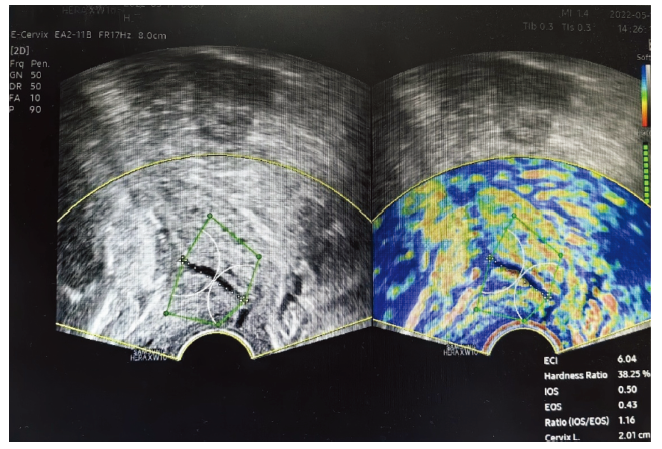

目的: 分析宫颈Bishop评分联合宫颈超声弹性成像技术及血清学标志物对宫颈成熟度的预测价值。方法: 回顾2022年1—6月在北京大学第三医院产检分娩、需接受引产的孕妇178例,于引产前测定宫颈超声弹性成像指标、血清学标志物(松弛素、雌二醇、雌三醇、孕酮)、宫颈Bishop评分,根据最终分娩结局分为引产成功组158例和引产失败组20例。比较2组上述指标的差异,并利用受试者操作特征曲线(receiver operator characteristic curve,ROC曲线)分析联合检测对宫颈成熟度评估的价值。结果: 引产失败组弹性对比指数(elastic contrast index,ECI)、宫颈外口应变平均值(external cervical os,EOS)和松弛素水平低于引产成功组,宫颈长度长于引产成功组(P<0.05),2组间孕酮、雌二醇和雌三醇水平比较差异无统计学意义(均P>0.05)。宫颈Bishop评分联合超声弹性成像指标(ECI、EOS、宫颈长度)及血清松弛素时对宫颈成熟度的评估价值最高,ROC曲线下面积为0.940。结论: 宫颈Bishop评分联合宫颈超声弹性成像和松弛素检查可提高预测宫颈成熟的准确性。

Objective: To analyze the predictive value of cervical Bishop score combined with cervical ultrasound elastography and serological markers for cervical ripening. Methods: 178 pregnant women who were registered at Peking University Third Hospital from January 2022 to June 2022 and underwent induced labor were selected and divided into a successful labor induction group of 158 cases and a failed labor induction group of 20 cases. Cervical ultrasound elastography indexes, serological markers (relaxin, estradiol, estriol, progesterone), cervical Bishop score before induction of labor were collected and analyzed. Compare the differences in the above indicators between two groups, and use the receiver operator characteristic curve (ROC curve) to analyze the value of combined detection in evaluating cervical ripening. Results: The elastic contrast index (ECI), external cervical os (EOS) and relaxin levels of the failed labor induction group were lower than in the successful labor induction group, and the cervical length was longer than that in the successful labor induction group (P<0.05). There was no significant difference in the levels of progesterone, estradiol and estriol between the two groups (P>0.05). The combination of cervical Bishop score, ultrasound elastography indicators (ECI, EOS, cervical length), and serum relaxin had the highest evaluation value for cervical ripening, with an area under the ROC curve of 0.940. Conclusions: The cervical Bishop score combined with cervical ultrasound elastography and relaxin can improve the accuracy of predicting cervical ripening.